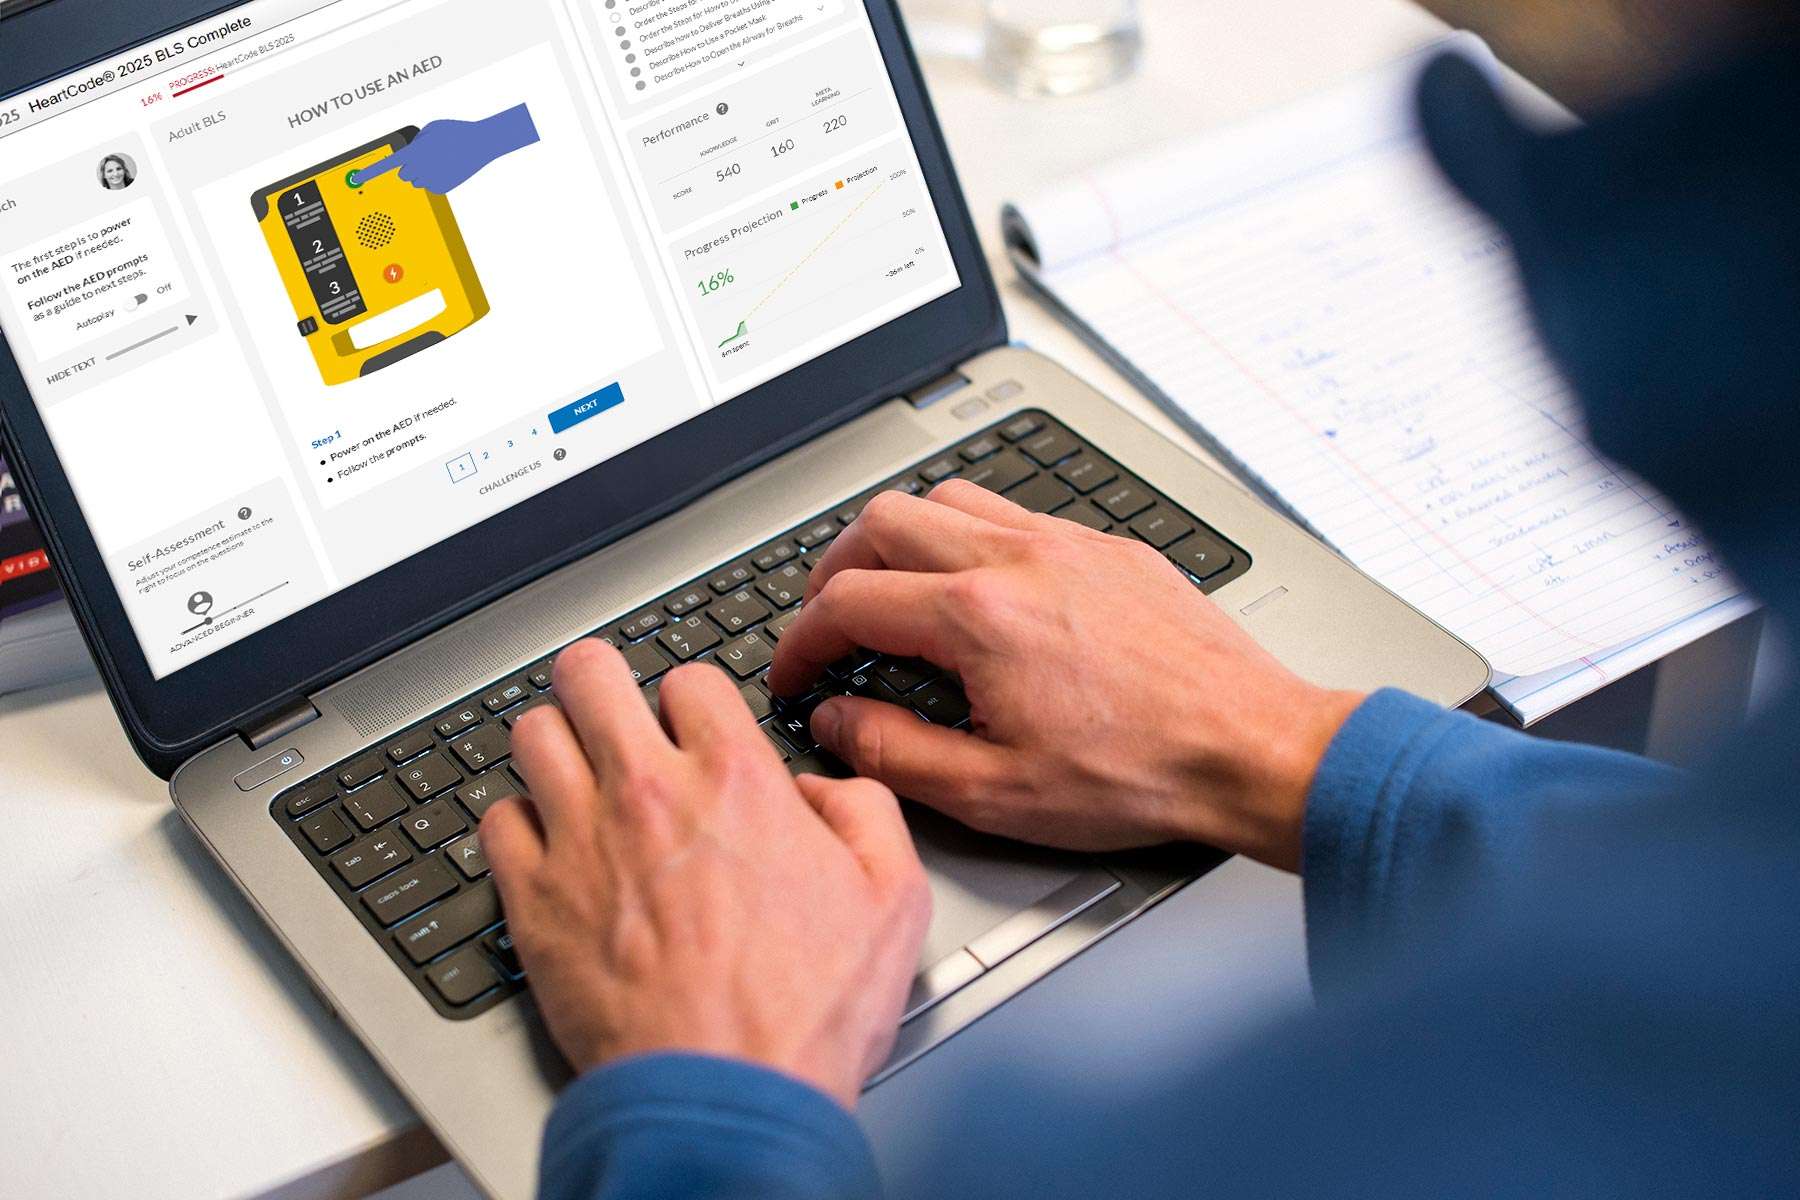

- 我国成人心肺复苏术普及率仅在1%左右,而美国是60%;

- 心肺复苏术的及时(黄金四分钟)、高质量实施能让无数人重获生命,也是提高心脏骤停存活率的关键。